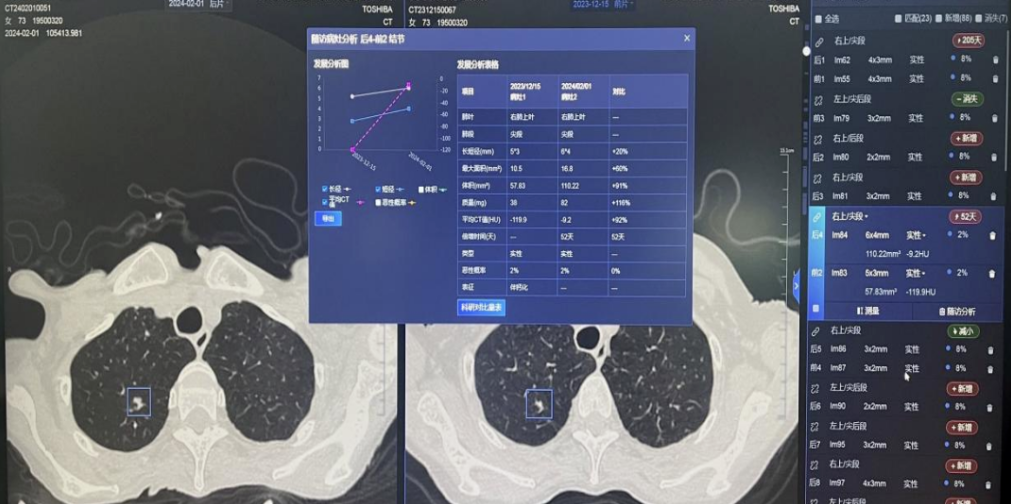

AI助力肺结节智能筛查

一次胸片CT检查至少会产生几百上千幅图像,早期的肺结节可能仅有几毫米大小,人工智能(AI)医学辅助诊断系统从这些CT图像中发现结节,并能精准量化结节大小,判断结节性质,给出结节危险度判定,并精准定位至肺叶、肺段,进行智能随访,辅助医师做出临床诊断和决策。